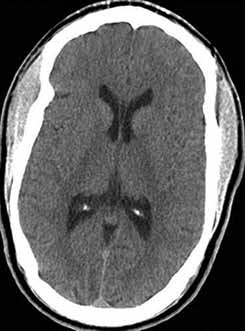

Reccurent Headaches in a 31-yr-old Woman

CT scan of the head without contrast is obtained and is shown. Which of the following is a correct reading of the CT scan?